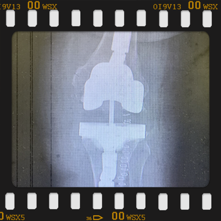

Eklem yüzeyleri özel kılavuzlar yardımı ile temizlendikten sonra metal protez eklem yüzeylerine bir kemik çimentosu ile adapte diyoruz. Bu iki metal yüzeyin sürtünmesini azaltmak için polietilenden yapılmış özel bir plastik tabakayı sisteme dahil ediyoruz.

Büyütmek için üzerine tıklayınız.